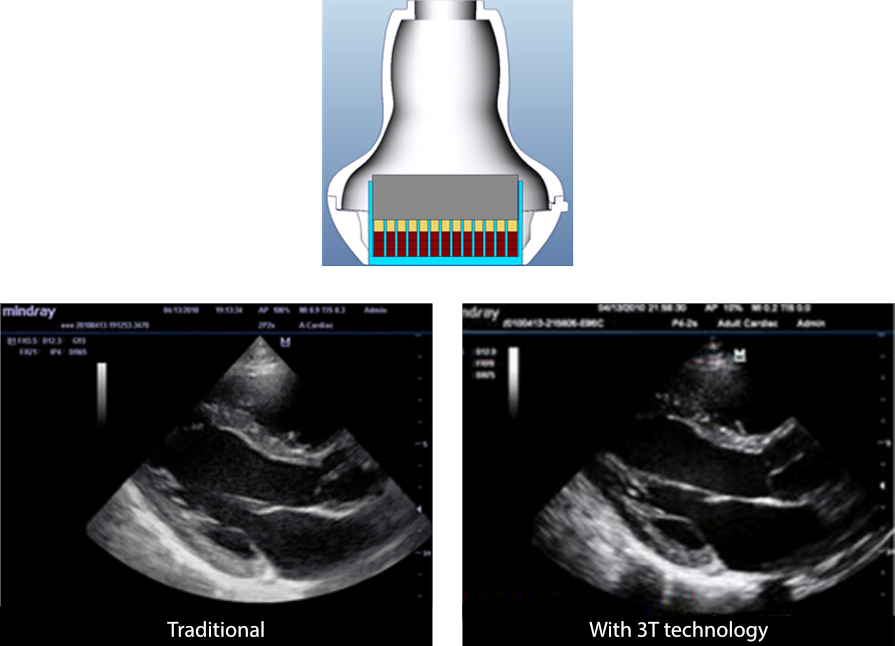

3T Transducer Technology?

Mindray-transducerpatenttechnologie voor grotere beeldbandbreedte en transmissie-effici?ntie.

┬Ę Drielaags ontwerp voor grotere gevoeligheid, grotere bandbreedte en betere S/N

┬Ę Total-cut-ontwerp voor minder overspraakruis, betere gerichtheid en verbeterde laterale resolutie

┬Ę Warmteregelingontwerp voor betere akoestische transmissie